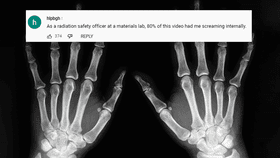

With the equipment, which came to much less than the hospital charged his insurance for his single X-ray, he was able to produce a pretty good image of a finger bone he happened to have lying around the house.

"That's actually pretty good," interventional radiologist Dr Michael Cellini said in a reaction video, though he pointed out it was nowhere near the standard of image that you'd receive in hospital – the high-quality you need for diagnosis. "I'm pretty impressed for just being in your garage," he said.

However, the radiologist (and other radiologists online) were less impressed when he chose to X-ray his own hand. Osman points out that the radiation that he'll receive from his X-ray is not as bad as a CT scan, or from a year of living your life being bombarded by background levels of radiation.

"The X-rays produced are not as bad as a CT scan – but that doesn't mean you should do it," Dr Cellini confirmed. "It is probably less than what you'd get from an annual background radiation dose. There is risk, but not as high as you'd think."

The video received less of an enthusiastic reaction from experts commenting on his video, where one wrote "[A]s a radiation safety officer at a materials lab, 80% of this video had me screaming internally", nor on the Radiology subreddit where a popular comment read "[E]very radiologist watching this is rolling their eyes so far back they can see their optic nerve."